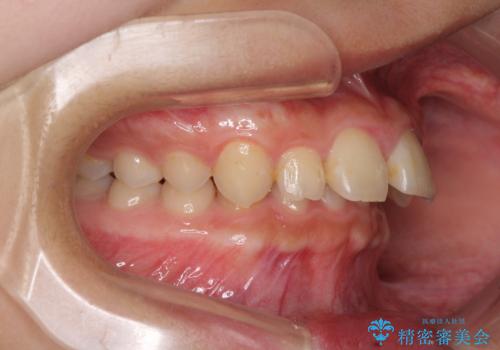

当院では通常、臼歯の咬合が理想的な位置に対して上顎が前方位にある場合。ワイヤー矯正または補助装置の併用したインビザライン矯正を選択しています。

正面や横からの写真ではきれいに治っており、患者様は大変満足のいく仕上がりとなりましたが、深い咬み合わせの改善は不十分で、奥歯の咬み合わせも改善させることができませんでした。

インビザラインは、咬合力の強い方ですと、奥歯が歯肉内にめり込んでしまうため、前歯が強く接触してしまうことがあります。

こちらの方は、奥歯はしっかりと噛んだのですが、歯肉にめり込んでしまったことで、歯肉が腫れやすくなってしまいました。